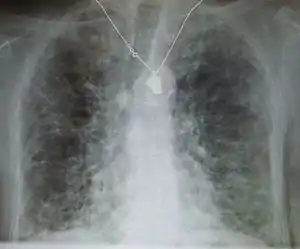

![]() | |

| عکسی از قفسه سینه با فیبروز ریوی که ناشی از آمیودارون تشخیص داده شده. | |